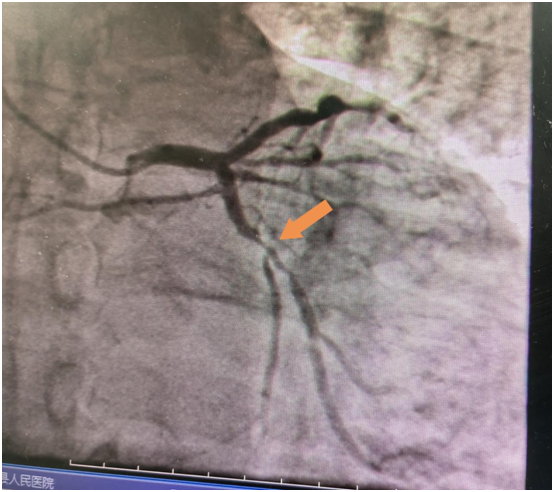

60岁的吴老伯患高血压病4年多,平时口服降压药物,没有规律监测血压,3年前患脑梗,治疗后好转,没有遗留明显后遗症,出院后没有规律服用药物治疗,出院时医师反复交代戒烟,吴老伯也没有放在心上。最近吴老伯在于熬夜后感头痛不适,起初头痛能自行缓解,随后感头痛症状反复发作,在快步行走及爬楼梯时明显,休息10多分钟可缓解,因症状反复发作,来到开阳县人民医院就诊,心血管内科医师在详细询问病史后,考虑吴老伯是冠心病高危人群,且头痛与活动相关,高度怀疑心绞痛,建议住院治疗,最开始吴老伯还很纳闷,明明是头痛来看病,怎么就变成心绞痛了?我没有胸痛啊!虽然心里有疑问,吴老伯还是接受医师的建议住院完善冠脉造影检查,果然冠脉造影明确了心脏回旋支有弥漫性狭窄,狭窄最重85%,前降支狭窄最重处75%,明确了头痛原因就是心绞痛。随即,心内科介入团队为吴老伯进行了回旋支支架植入术。植入支架后,吴老伯活动时头痛的症状也消失了。可以回家过个安稳的春节了。

冠脉造影结果

支架置入术后效果